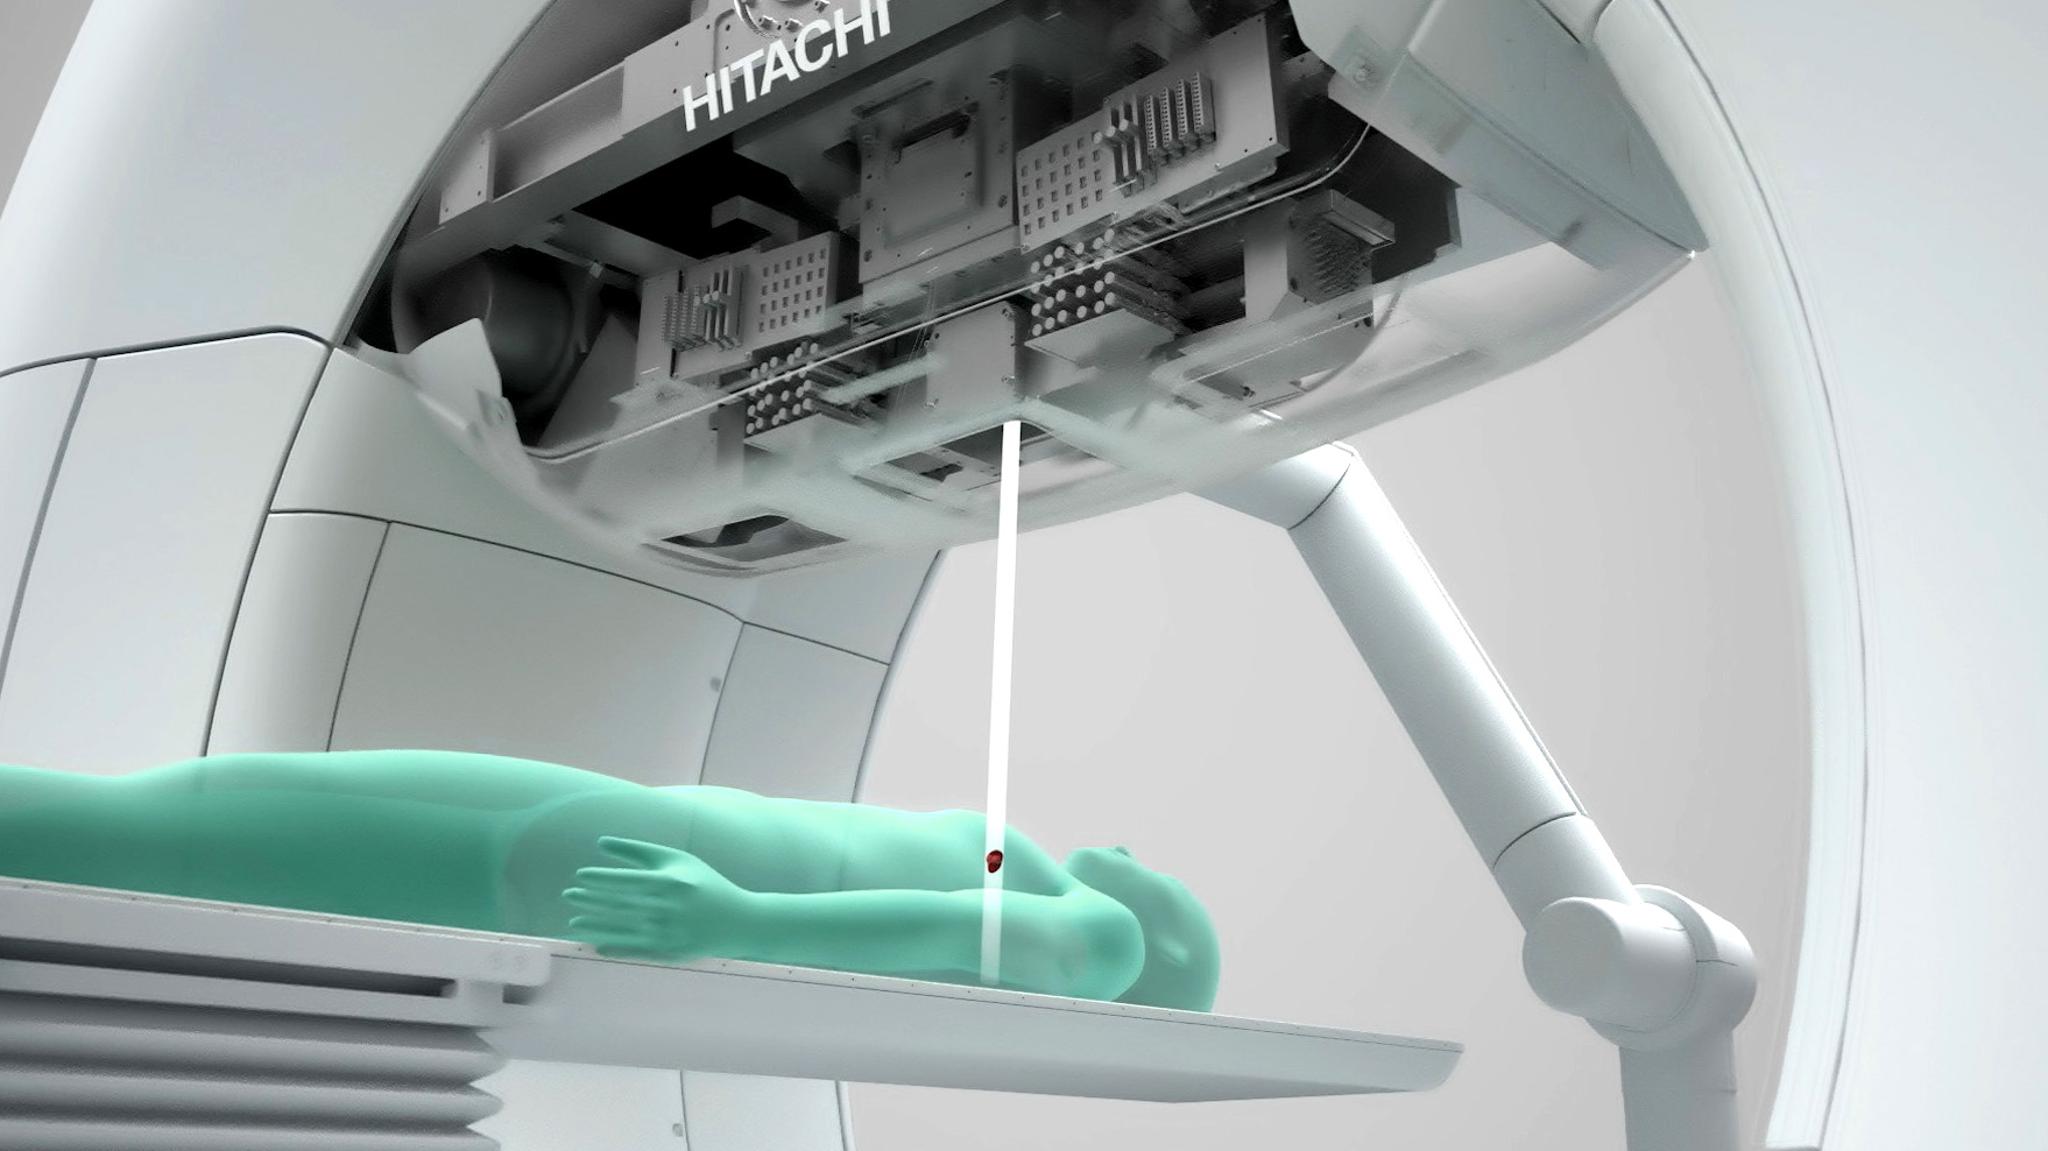

Hitachi High-Tech, Ltd.The OXRAY is a cancer treatment system in which the stage and the inside of the gantry rotate on two axes to deliver X-rays from various angles. The gimbal function enables dynamic tracking of cancer tissue that moves with respiration, which reduces the physical burden and enables high-precision treatment. This reduces side effects and treatment time. In addition, the irradiation range has been expanded to accommodate more cases, and throughput has been significantly improved by integrating individual systems. As of 2025, the system will be available only in Japan.